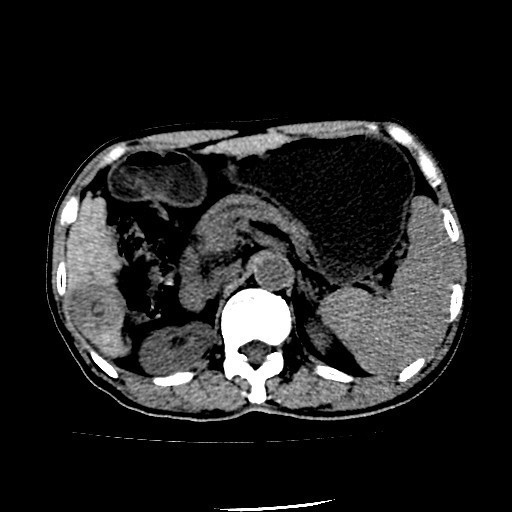

查体:肝脏剑突下4cm可触及,质中。移动性浊音可疑阳性,肠鸣音正常。 辅助检查:外院查MR示:肝脏右叶后下段团块影,直径约3.6cm,考虑肝癌;肝硬化、脾大,多量腹水,考虑门静脉高压。

诊断:1、肝细胞癌 2、肝炎后肝硬化(乙肝)、门静脉高压、脾大、腹水。 治疗:入院复查CT示:1、肝S6段结节型肝癌。2、结节型肝硬化;门脉高压,食管胃底静脉、胃管状静脉、脾静脉曲张;脾稍大;少量腹水。 遂排除手术禁忌症,于全麻下行肝S6段肝癌切除术,术后病理示:(肝S6段肿物)形态结合免疫组化,符合高~中分化肝细胞性肝癌,未见确切脉管内癌栓形成;“切缘”未见癌;周围肝组织呈结节性肝硬化改变。免疫组化结果(⑦):Hep(+),Gly-3(部分+),CK7(-),CK19(-),CD34(肝窦毛细血管化),Ki-67(平均15%+)。术后继续患者肝功能逐渐恢复,腹水逐渐吸收。